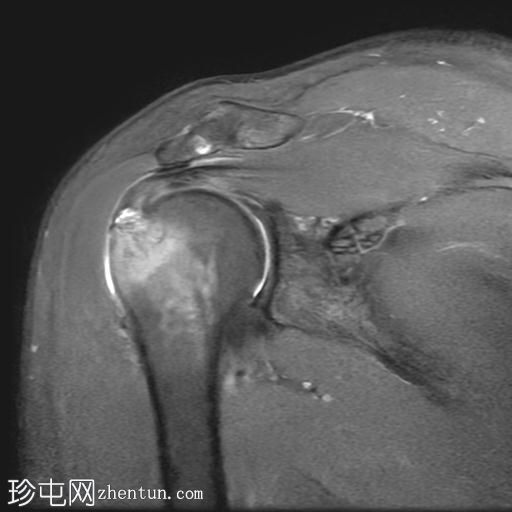

冠状位

T2加权像

T1加权像

冈上肌腱关节面中前部纤维可见部分撕裂(边缘撕裂),伴局部骨髓水肿。

冈上肌腱关键区纤维以及冈下肌腱均可见肌腱病。

肩锁关节周围可见轻度关节囊肥厚和退行性改变。

此外,肩峰下滑囊内可见积液。

MRI 检查结果符合冈上肌腱的典型边缘撕裂,也称为部分关节面肌腱撕脱。